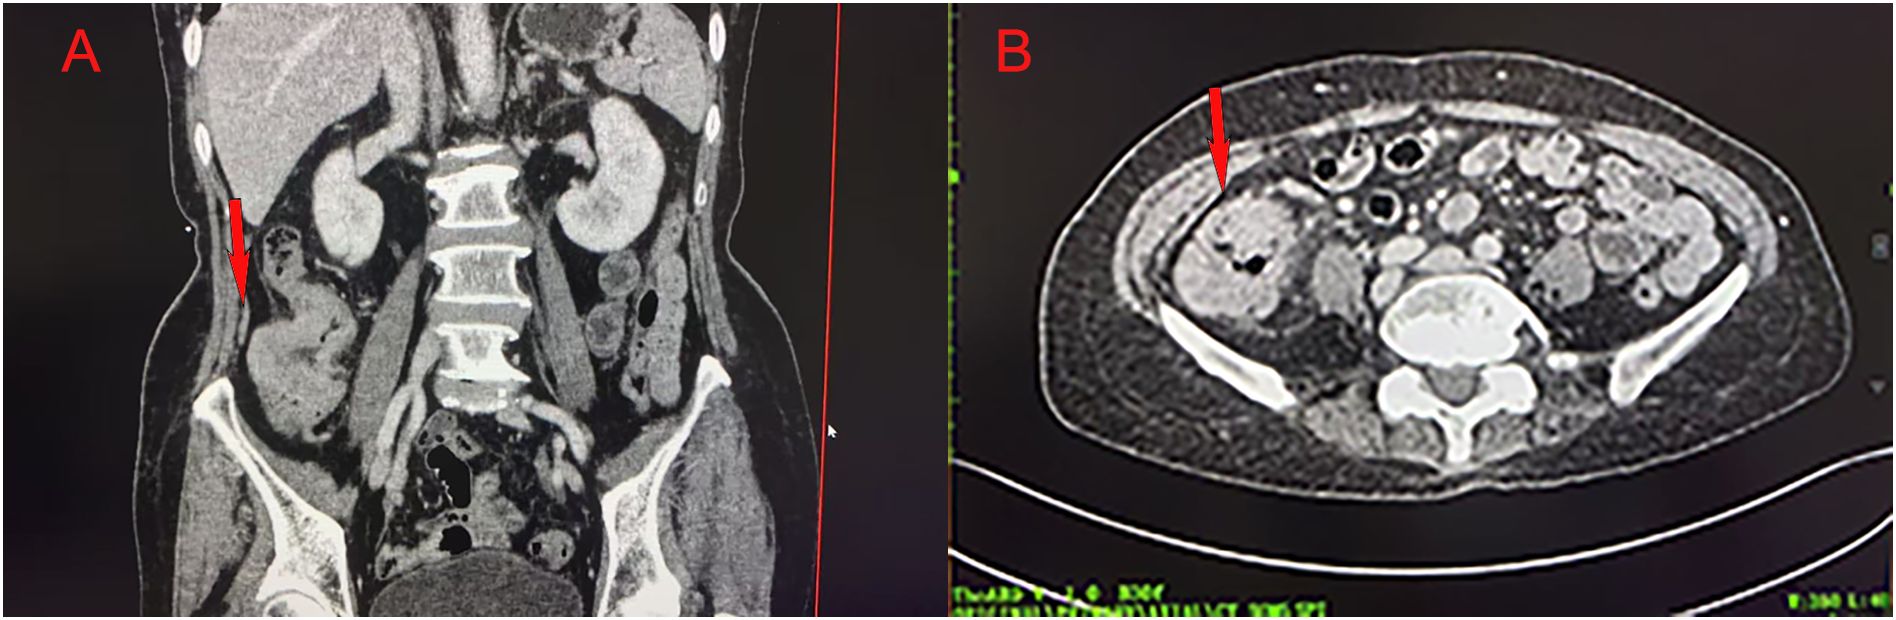

Colonoscopy demonstrated an ulcerative stricture in the ascending colon, and histopathological examination of the biopsy confirmed poorly differentiated adenocarcinoma (Figure 1). Imaging studies, including thoracoabdominal computed tomography (CT), revealed an ascending colon mass with mildly enlarged regional lymph nodes (Figure 2). The patient had no significant comorbidities, and preoperative cardiopulmonary evaluation confirmed suitability for surgery.

Figure 1. Colonoscopic showing an ulcerative stricture in the ascending colon.

Figure 2. Abdominal CT showing an ascending colon mass in coronal (A) and axial (B) views.